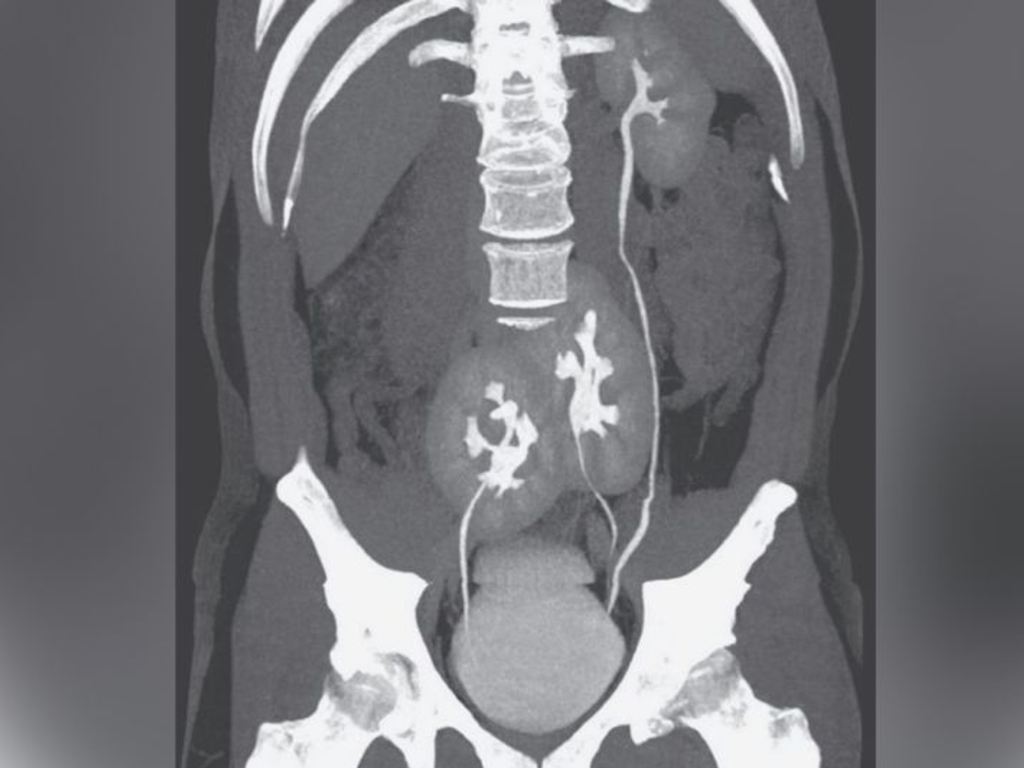

A man in Brazil learned he had three kidneys after receiving a CT scan for low-back pain. Above, the CT scan showing the man’s three kidneys: A normal-appearing kidney on the man’s left side, and two kidneys fused at the pelvis. The New England Journal of Medicine

Humans typically have two kidneys, but this man had one normal-looking kidney and two fused together, near his pelvis, the report says.